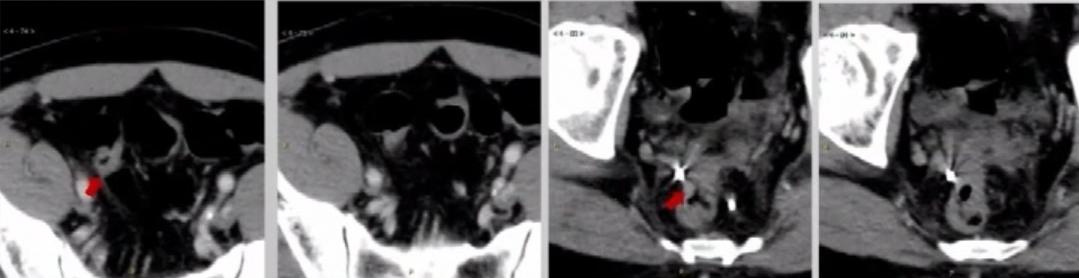

2019.1.16盆腔增强MR

1. 上段直肠癌,MR分期拟T4bN0M1,MRF(+),EMVI(-);

2. 乙状结肠癌,MR分期拟T3aN0M1。